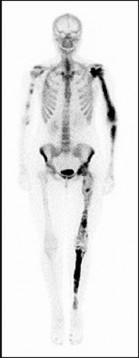

Figures 9a through 9d are the anteroposterior and lateral radiographs, CT scan, and technetium bone scan of a 12-year-old boy who has experienced 7 months of pain in his lower leg. The pain limits his ability to participate in sports and he is having difficulty sleeping. He is afebrile, and laboratory study findings including an erythrocyte sedimentation rate, C-reactive protein, and complete blood count are within normal limits.

The images and clinical history support a diagnosis of osteoid osteoma, which most commonly occurs in adolescence. Although these lesions can be seen in any bone, they are usually located in the femur and tibia. The significant inflammatory response to this tumor is secondary to high levels of prostaglandin production. Characteristic night pain is relieved with nonsteroidal anti-inflammatory drugs (NSAIDs) or by aspirin.

Radiographic images show thickened bone and a small central nidus. Thin-cut CT scan is the imaging of choice to visualize the nidus. A bone scan is associated with uptake but is not specific. Treatment options include expectant management with NSAIDs and observation under the premise that these lesions eventually burn out. Contemporary treatment involves RFA. Historically, these lesions were treated with en bloc resection; however, this technique has largely fallen out of favor because of the high efficacy and comparative low morbidity associated with RFA.

When an osteoid osteoma occurs in the spine, it is located in the posterior elements, and paraspinal pain and scoliosis often are present.